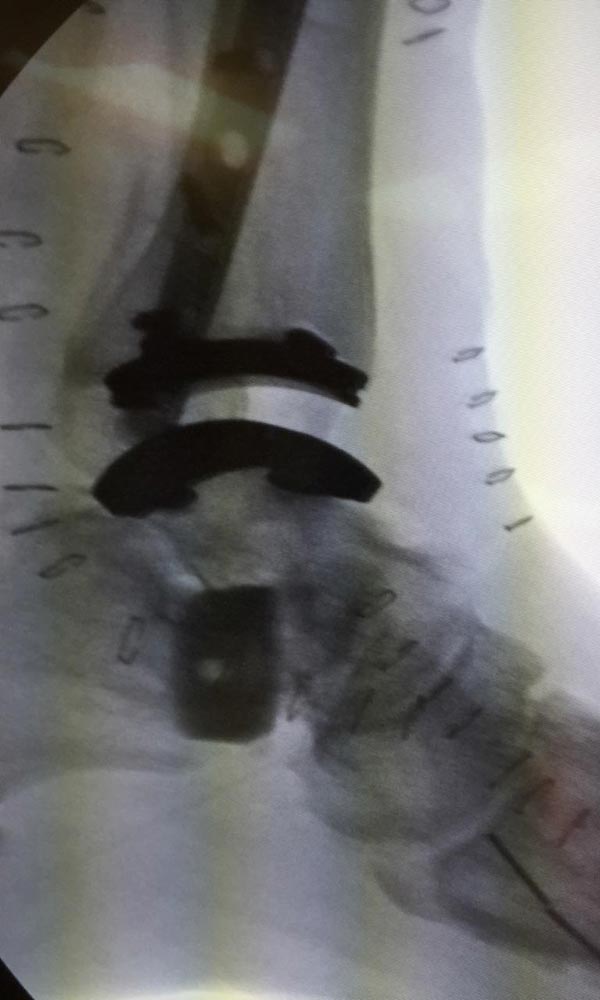

Ten years of severe ankle pain with a mal-positioned ankle fusion is now relieved! Patient is now walking with pain-free ankle motion!